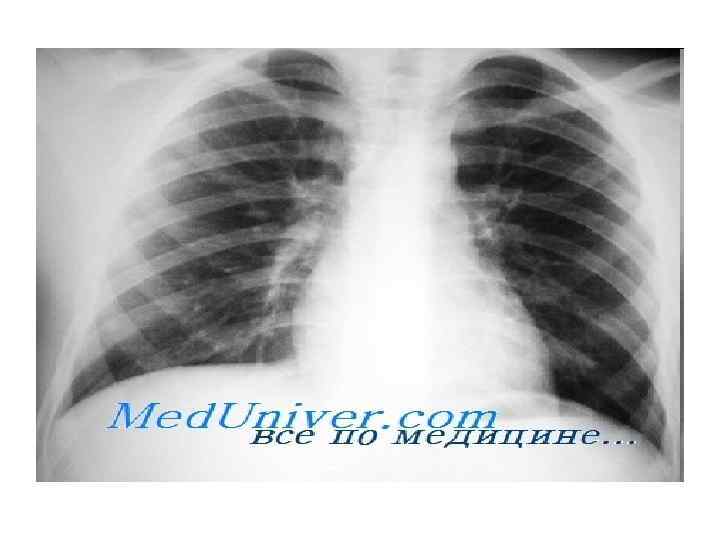

Введение Исследование сердца следует производить системно. После оценки общего размера сердца и сосудистого рисунка легких, отражающих физиологический статус левых отделов сердца, необходимо оценить камеры сердца отдельно. На стандартной рентгенограмме грудной клетки невозможно четко различить эти камеры. Более того, часто при желудочковой недостаточности увеличивается тень сердца, но увеличение конкретной полости сердца не заметно.

Тем не менее приобретенных заболеваниях клапанов сердца и многих врожденных болезнях сердца отдельные камеры сердца увеличиваются значительно и становятся заметными на обзорных рентгенограммах (и часто клинически). В настоящее время такую информацию можно получить с помощью других, более дорогих способов визуализации, в частности эхокардиографии, магнитного резонанса сердца (МРС) и компьютерной томографии. Однако обычные рентгенограммы все еще не потеряли свою актуальность, т. к. они позволяют быстро, доступно, четко и относительно недорого объективно оценить состояние и проследить его динамику.

Правое предсердие на рентгенограмме. Увеличение правого предсердия никогда не бывает изолированным, за исключением случая врожденной атрезии трикуспидального клапана или аномалии Ebstein. У взрослых ПП может быть расширенным при ЛГ или регургитации крови через трехстворчатый клапан, но расширение ПЖ обычно преобладает, что препятствует визуализации ПП. Контур ПП сливается с ВПВ, правой главной ЛА и ПЖ.

Правый желудочек на рентгенограмме. Классическая картина увеличения правого желудочка: сердце в виде «башмака» , заполняющее собой ретростернальное пространство. Такая форма возникает из-за поперечного расширения верхушки ПЖ вследствие дилатации. Для взрослых изолированная дилатания ПЖ без расширения ЛЖ нетипична, поэтому форма в виде «башмака» встречается нечасто. Чаще всего это единственная находка при врожденном пороке сердца — классической тетраде Fallot.

При дилатации правый желудочек расширяется не только вверх, по и вбок и кзади, заполняя ретростерналыюе воздушное пространство. Считается, что плотность мягких тканей на обычной боковой рентгенограмме грудной клетки не превышает 1/3 расстояния от яремной вырезки до верхушки мечевидного отростка. Если же мягкие ткани занимают больше 1/3, то при отсутствии других причин это служит убедительным доказательством увеличения ПЖ. Другие причины увеличения мягкотканного уплотнения в зоне ПЖ обычно определяются легко.

Наиболее распространенные причины и обычно легко отличаемые от увеличения правого желудочка — ретростернальные адепопатии, опухоли средостения (лимфома или тимома), заметное расширение ствола легочной артерии и значительное расширение корня аорты. Наиболее распространенная причина увеличения загрудинно расположенных мягких тканей — это срединная стернотомия в анамнезе с образованием рубцов и нечеткости в этой области. Чаще всего увеличение ПЖ отмечается при патологии митрального клапана и вторичной легочной гипертензии. Реже это бывает результатом первичной легочной гипертензии.